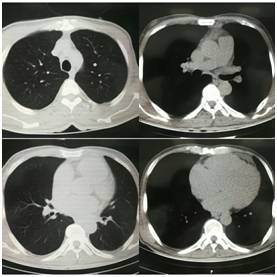

CT

入 院 诊 断

扩张型心肌病

心脏扩大

心功能IV级

肺部感染